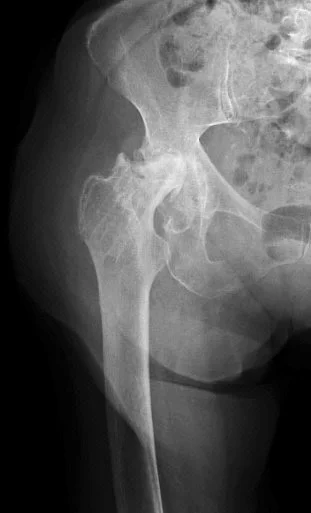

A 65 year old: slipped in the toilet

A 55 year old, tripped at edge of carpet

Radiological Evaluation

- Radiological evaluation

- AP and ?Lateral (cross-table)